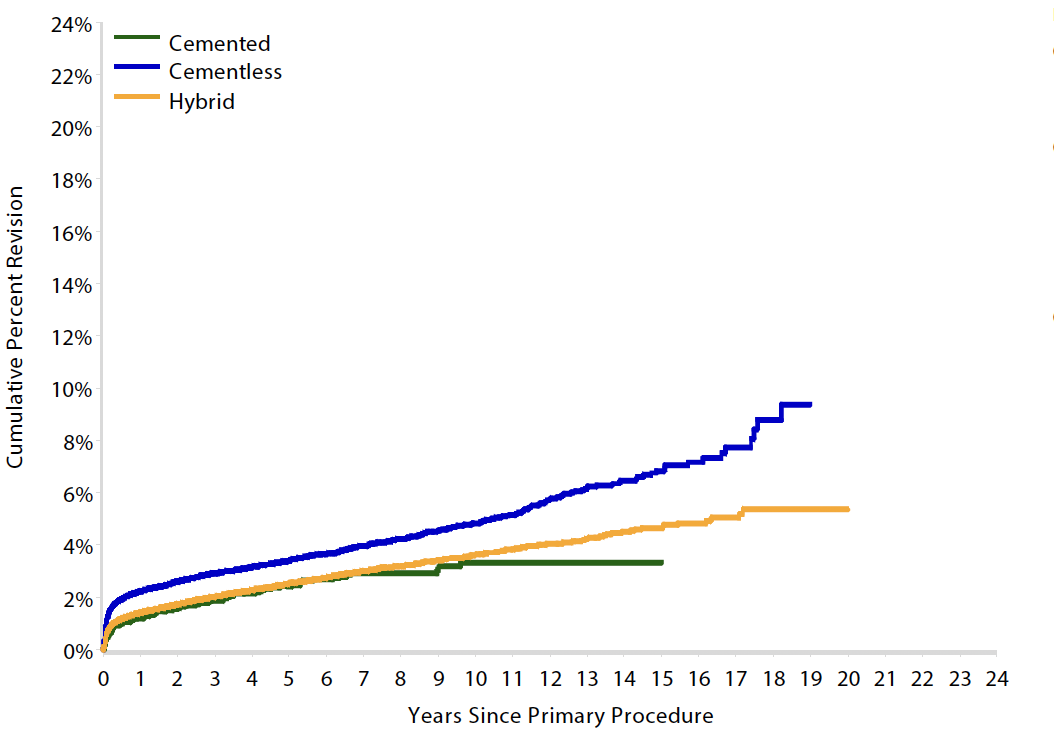

Australian Joint Registry 2023

- 15 year revision rate

- collared 5.3%

- collarless 6.0%

Results

Australian Joint Registry 2023 Revision rates by fixation (400,000 THA)

| Cemented | Uncemented | Hybrid | |

|---|---|---|---|

| 5 year | 2.6 | 3.0 | 2.6 |

| 10 year | 3.8 | 4.3 | 3.9 |

| 15 year | 5.1 | 5.9 | 5.3 |

| 20 year | 7.0 | 6.7 |

15 year revision rate by age

64 - 74 year > 75 years

| Cemented | Uncemented | Hybrid | |

|---|---|---|---|

| < 55 | 6.4 | 7.2 | |

| 55 - 64 | 6.2 | 5.5 | 6.1 |

| 65 - 74 | 5.4 | 5.5 | 5.2 |

| > 75 | 3.3 | 6.8 | 4.7 |